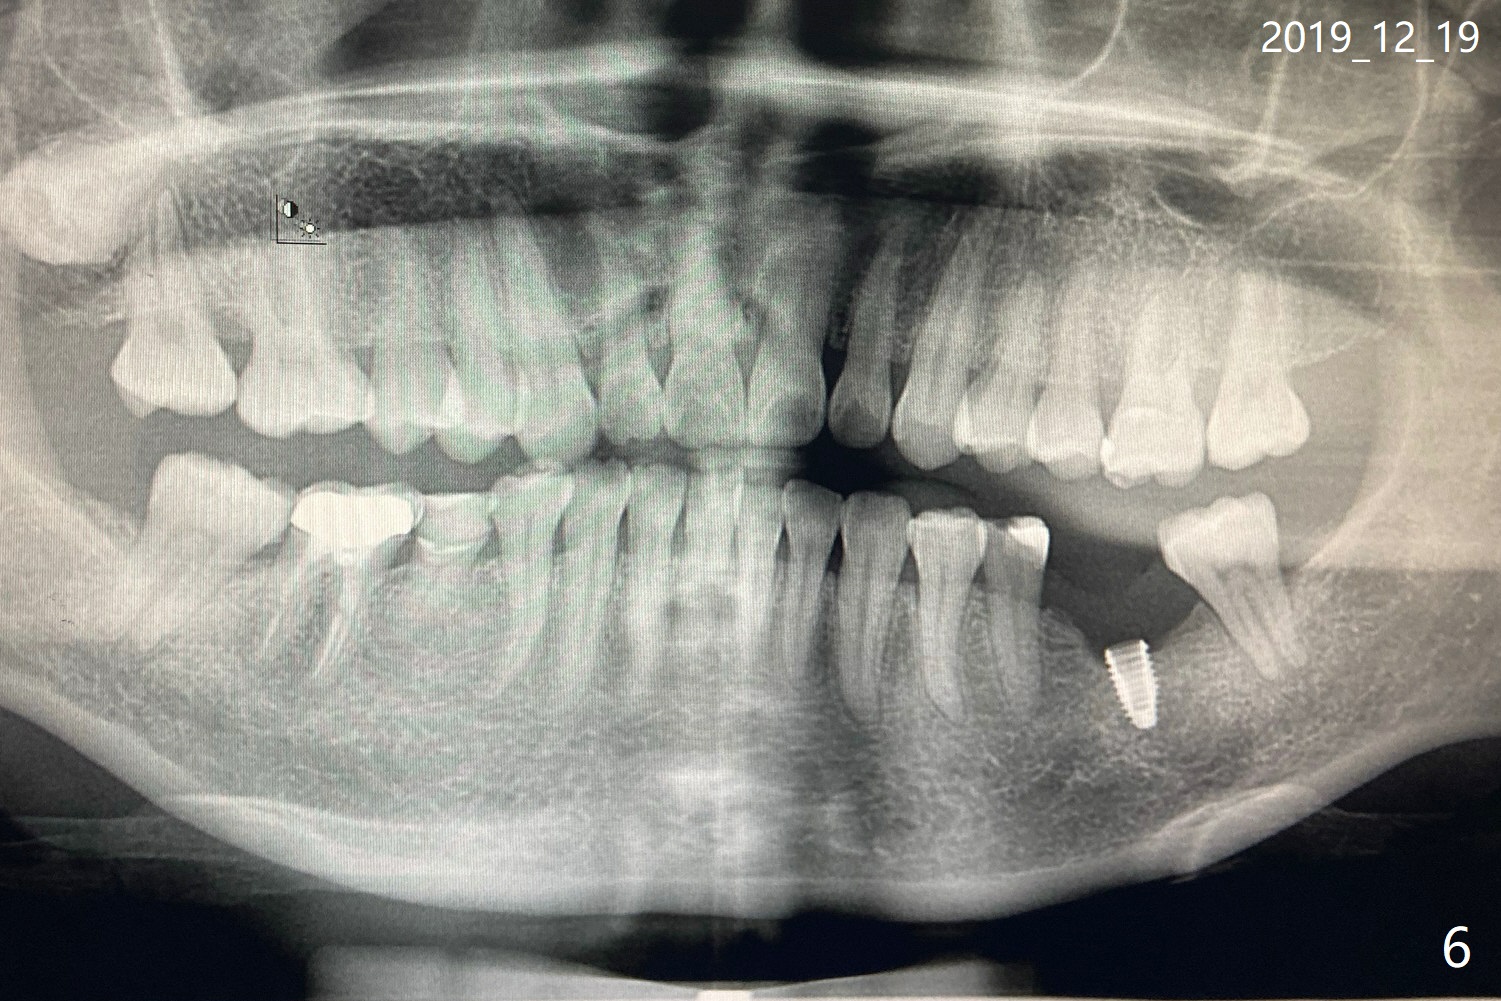

这边我找到有Neo种植体的诊所了,可那医生说应该植骨,重种。您能把我在美国时刚做完植体和装上牙冠后的x片发给我吗?我也把12月1号,8号和14号的x片发给您(图三至五). 另外,植体里的螺丝会磨没了吗? December 14, 2019, 3:21:23 AM EST

这边医生说我有种植体牙周炎,不能装healing abutment。今天给放上了一个钉子。您看我发的照片了吗(图六,七)?请指示

Dec 19 at 2:46 AM

由于手头资料少,很难帮你判断,能请医生拍摄根尖片或者CT检查?如果种植体周围炎诊断正确,他们的建议?最好我少提出建议,影响你与他们配合。临床情况复杂,鞭长莫及 Dec 19 at 1:42 PM